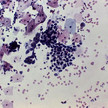

Fakten über Krebs Fangscheren und Feuerbohrer

Jeder kennt Krebs. Jährlich erkranken allein in Deutschland mehrere hunderttausend Menschen an einer der vielen Krebsarten. Neben einer Menge von Wissen gibt es... Mehr»

Mineralstoffe Pankreaskrebs durch Magnesiummangel

Magnesium senkt das Krebsrisiko. Diese These wird in lang angelegten Studien untersucht. Eine gerade veröffentlichte Arbeit zeigt den positiven Einfluss des... Mehr»

Neuroblastome Diclofenac gegen Krebs

Diclofenac könnte in der Krebstherapie an Bedeutung gewinnen. Wissenschaftler aus Belgien und den USA haben nach einer umfangreichen Analyse von In-vitro- und... Mehr»